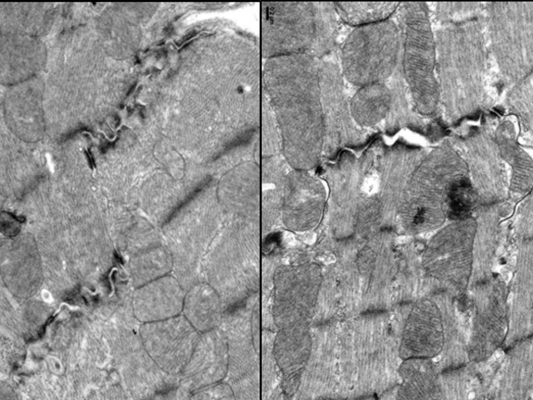

左圖為使用小紅莓治療後的小鼠心肌細胞,黑色類似峽谷的地方為心肌受損;右圖使用橙皮素後可看見受損的地方慢慢復原。照:國立陽明交通大學提供

研究團隊發現,小紅莓會抑制心肌細胞中長壽基因CISD2的表現,使粒線體與鈣離子調控失衡,導致心臟收縮與節律出現問題。相反地,橙皮素可以重新啟動長壽基因CISD2,減少心肌細胞受損。